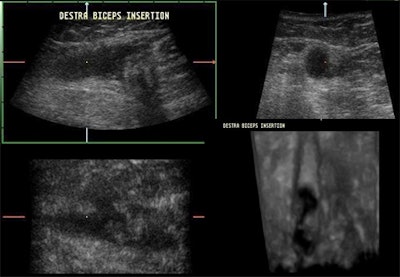

![]() |

| A lengthways split results in two cords, giving the appearance of two tendons lying side by side over a variable length of the tendon, as may be seen in the multiplanar images above. |

| This 3D reconstruction confirms the existence of a lengthways split within the biceps tendon. Two cords are seen lying parallel within the bicipital groove. |